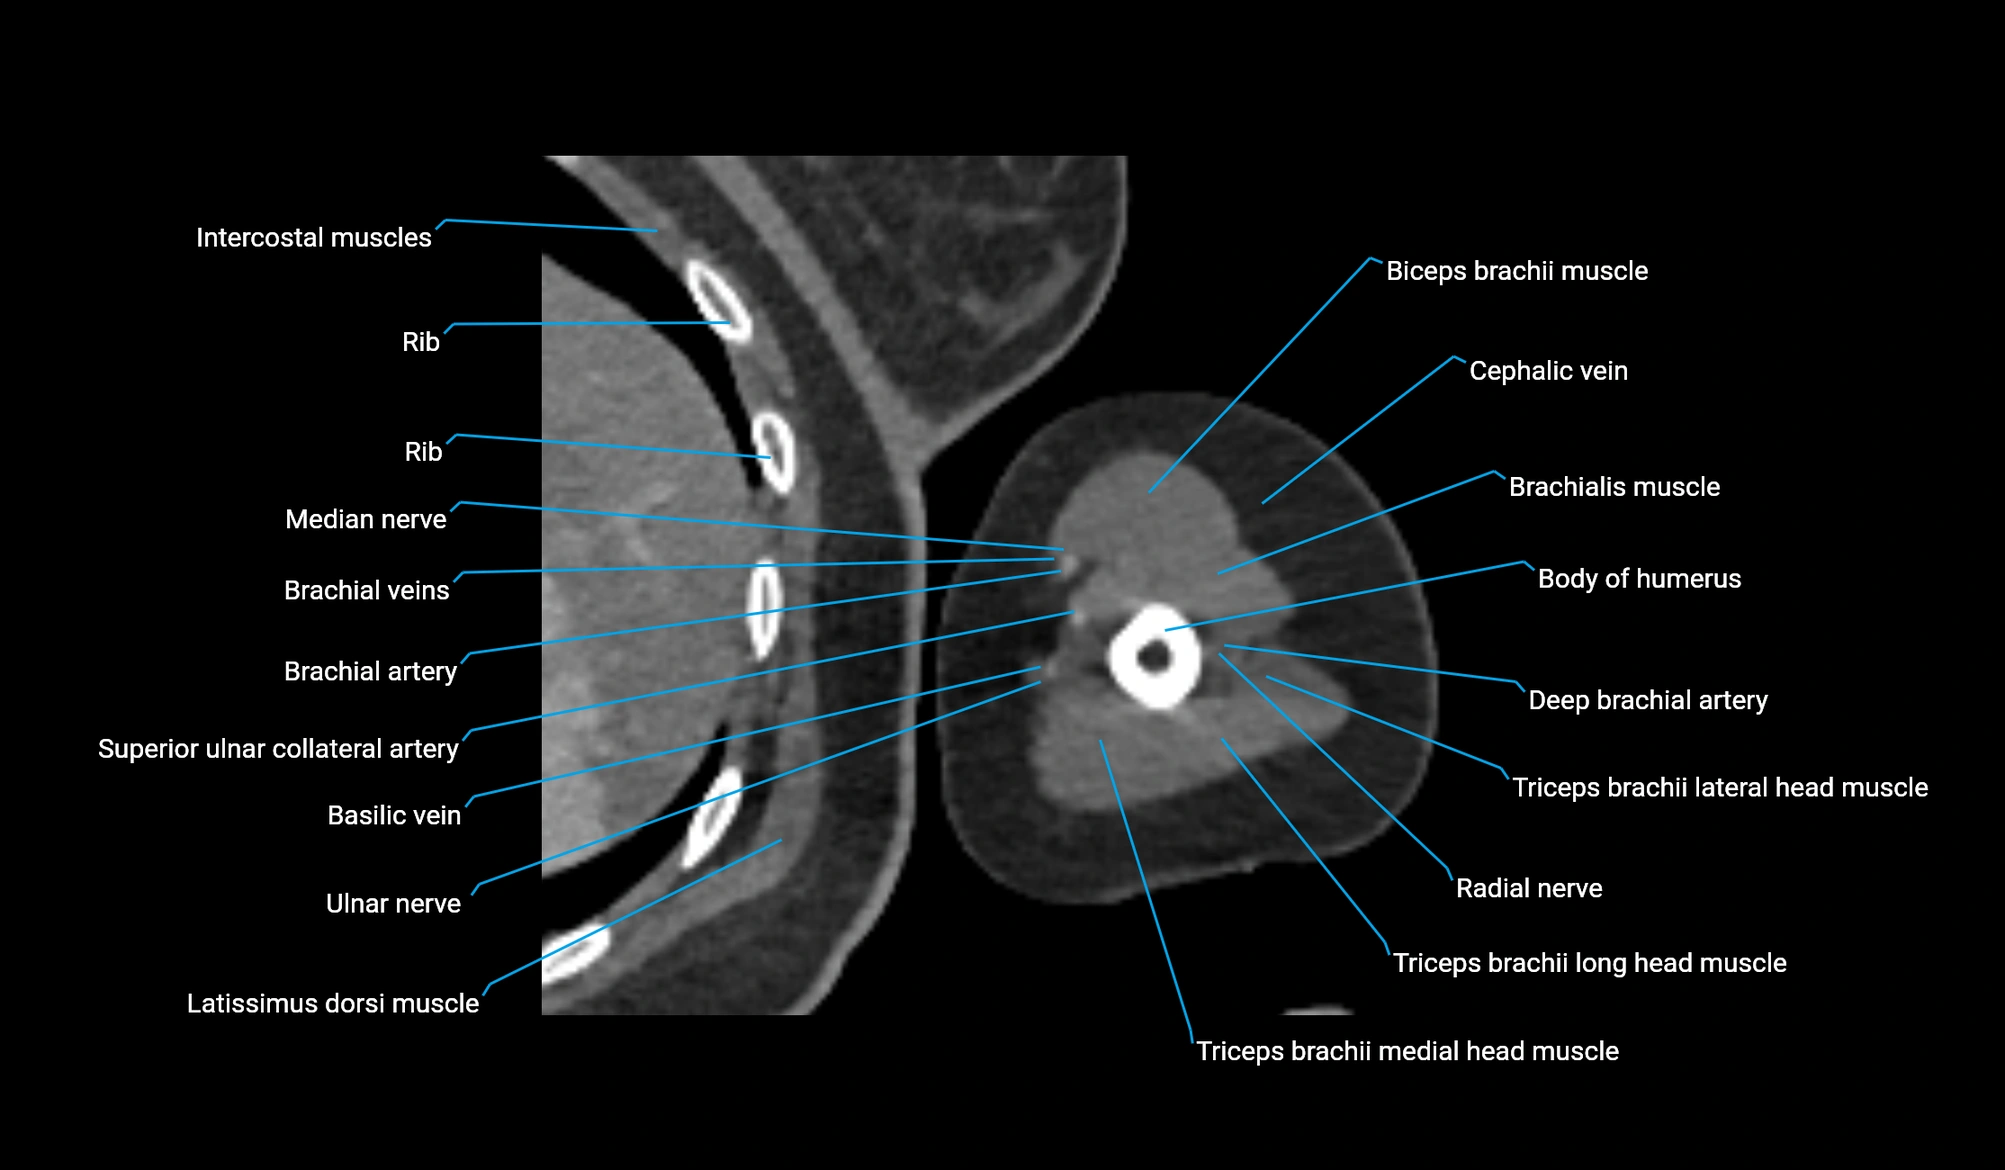

- Body of humerus

- Brachial artery

- Brachialis muscle

- Cephalic vein

- Deep brachial artery

- Lateral head of triceps brachii muscle

- Long head of triceps brachii muscle

- Medial head of triceps brachii muscle

- Median nerve

- Radial nerve

- Superior ulnar collateral artery

- Ulnar nerve